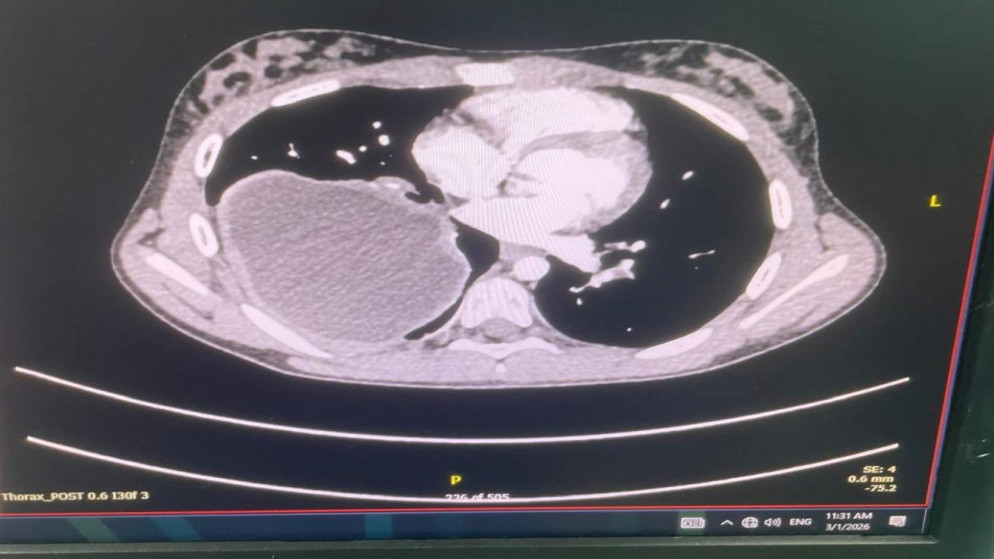

أفاد العميد الطبيب رازي أبو عنزة، رئيس الفريق الطبي، أن العملية شملت علاج انسلاخ في القوس والشريان الأبهري الهابط، وتوسع في الشريان الأبهري الصاعد، وارتداد في الصمام الأبهري، بالإضافة إلى تشوه في الشريان التاجي الأيمن.

قال مستشار جراحة القلب والأوعية الدموية إن العملية استغرقت 10 ساعات في المرحلة الأولى و3 ساعات في المرحلة الثانية، مبينا أن هذه العملية تعتبر من العمليات الأكثر تعقيداً في هذا المجال على مستوى العالم. وأضاف أنه خلال المرحلة الأولى تم استبدال القوس والشريان الأبهري الصاعد وجزء من الهابط، مع إعادة زراعة الشرايين المغذية للدماغ في عملية تعرف باسم "elephant trunk".

كما أشار المستشار إلى أنه تم خلال العملية إصلاح الصمام الأبهري وزراعة الشريان التاجي الأيمن. موضحا أنه في المرحلة الثانية، التي أُجريت بعد يومين، تم زراعة شبكتين في الشريان الأبهري الهابط.

أضاف المستشار أن إجراء هذه العملية تطلب تداخلات كثيرة ومعقدة، وتنطوي على خطورة عالية، خاصة في مرحلة تغيير القوس الأبهري. وأوضح أنه خلال هذه المرحلة يتم وضع كامل دم المريض خارج الجسم في جهاز القلب والرئة الصناعية، مع تبريد حرارة الجسم إلى مستويات منخفضة جداً مع الحفاظ على تروية دموية مستمرة للدماغ. مبينا أن العقيد الطبيب محمد الرواشدة والمقدم الطبيب سامر الجفوت، وهما استشاريا جراحة الأوعية الدموية والأشعة التداخلية، شاركا في العملية. وأكد أن المريض تماثل للشفاء وغادر المستشفى بصحة جيدة.